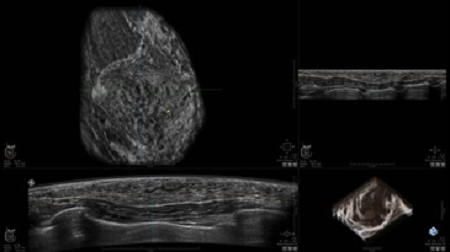

УЗИ-аппарат

GE INVENIA ABUS 2.0

GE INVENIA ABUS – это современный УЗИ аппарат, который создан для точной и эффективной диагностики сканирования с высокой плотностью молочных желез. Выявляемость патологий раковых и предраковых стадий заболевания составляет 55%, что в конечном счете позволяет ставить врачу точные и своевременные диагнозы. Традиционные методы использования маммографии не показывают такой выявляемости, ограничиваясь лишь 3-38%.

УЗИ-аппарат GE INVENIA ABUS позволяет проводить максимально операторонезависимые процедуры, что значительно снижает риск неправильной постановки диагноза и сопутствующие издержки на обработку информации. Система готовит отчет в течение 3-х минут после сканирования, это безусловное преимущество по сравнению с обычным УЗИ сканером.

• датчик с изогнутой апертурой для качественного исследования

• сканирование одной грудной железы в трех проекциях не более 60 сек.;

• обработка результатов за три минуты.

• Получение объемных 3D изображений с возможностью покадрового просмотра

• Получение изображений в поперечной плоскости (в реальном времени) и в коронарной плоскости (статическая, для указания нахождения соска)

• Отображение объемных 3D ультразвуковых изображений, которые состоят из традиционных поперечных и воссозданных коронарных и сагиттальных проекций

• Возможность отображения полного 3D изображения